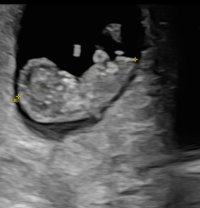

Fikk se et bankende hjerte idag, og målingene viste at jeg var nøyaktig like langt komt som jeg trodde

Ingen hjertebank da, men fikk beskjed om at det var for tidlig.